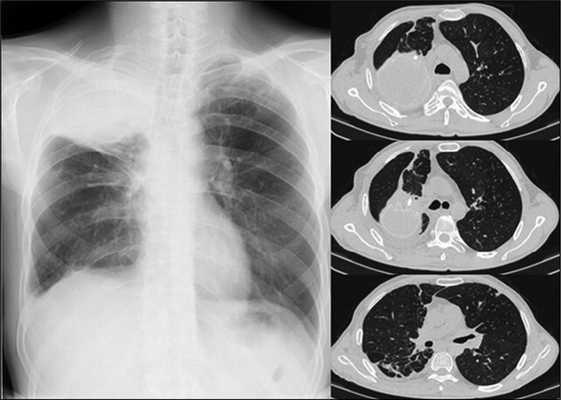

На обзорных рентгенограммах и компьютерной томографии легких определяется фиброзное сморщивание верхней доли и S6 правого легкого, S1-2 левого легкого. Множественные разнокалиберные тонко- и толстостенные каверны: крупные в верхних отделах и мелкие в нижних отделах правого легкого (рис. 1).

Рис. 1. Рентгенографическое (А) и КТ (Б) исследование органов грудной клетки у больного А. при поступлении (описание в тексте)

Рентгенографическое и компьютерно-томографическое исследование через 1,5 мес после операции: в динамике дальнейшее расправление правого легкого под пломбой. Дополнительных очагово-инфильтративных изменений в легких не выявлено (см. рис. 5).

Рис. 5. Рентгенографическое исследование от 04.07.16 и КТ органов грудной клетки от 22.06.2016 при выписке